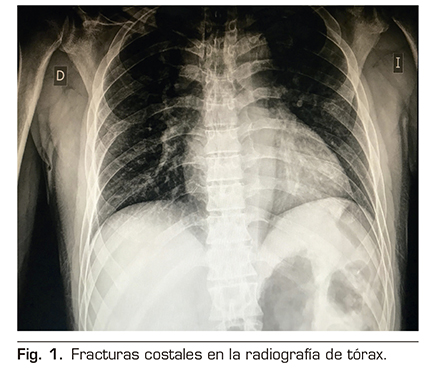

Se le realizó un bloqueo ecoguiado ESPB con colocación de catéter para analgesia continua posterior. Para ello, se colocó al paciente en posición de decúbito lateral derecho, y se procedió a la preparación de la zona de punción con povidona yodada, colocación de campo estéril y elección de sonda ecográfica lineal de alta frecuencia. Se identificó la apófisis espinosa de la 6.ª vértebra torácica y a una distancia de 3 cm lateral se identificó el proceso transverso de la misma. En la imagen ecográfica, visualizamos el plano subcutáneo y varios grupos musculares que de superficial a profundo corresponden con el músculo trapecio, romboides y erector de la columna, todos ellos sobre la apófisis transversa vertebral (Figura 2).